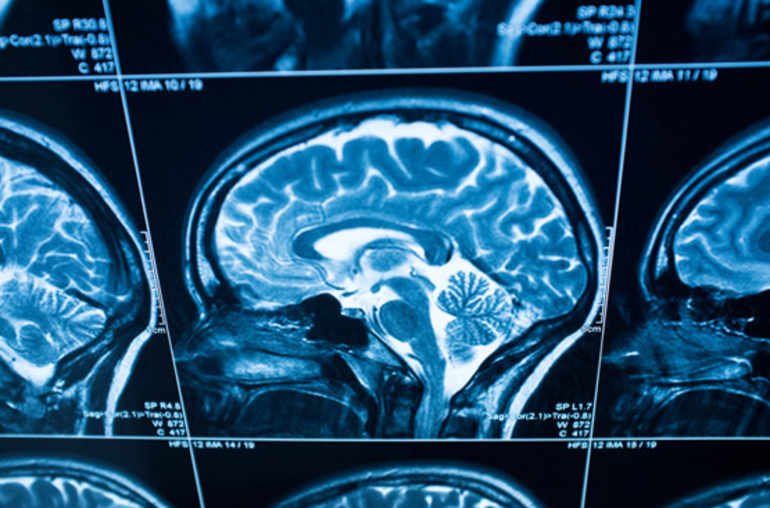

AVC: aider le cerveau à mieux récupérer

La technique en question a pour nom «optogénétique». On peut aussi parler de «stimulation cérébrale ciblée». Et les résultats des derniers travaux la concernant laissent espérer qu’elle contribuera à améliorer la récupération des personnes victimes de certains accidents vasculaires cérébraux (AVC): ceux d’origine ischémique, causés non pas par une hémorragie cérébrale, mais par l’oblitération d’une artère assurant la vascularisation d’une région des territoires cérébraux.

La technique de l’optogénétique est assez sophistiquée. Elle nécessite notamment d’avoir recours aux techniques de la thérapie génique, afin de rendre les cellules nerveuses sensibles à la lumière. Elle consiste ensuite à stimuler, par laser, la zone du cerveau qui contrôle la motricité. Cette zone est souvent sévèrement touchée après un AVC, ce qui peut entraîner des conséquences sur la motricité, la parole et certaines fonctions intellectuelles.

Les auteurs rappellent que cet espoir thérapeutique repose sur la «plasticité» du cerveau, soit sa capacité d’adaptation, voire de modification. On sait ainsi que lorsqu’une zone cérébrale est lésée, le cerveau peut «réparer» les «connexions» pour récupérer la fonction cognitive. C’est là une forme de «recâblage» qui peut prendre des mois ou plus. Pouvoir réduire les délais et augmenter le niveau de récupération est d’ores et déjà une perspective prometteuse.